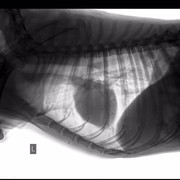

Собаке сделали операцию, но не на тазу (таз вправили ректально), а на передней лапе, которая оказалась сломана, но в виду того, что собака была лежачей и болезненно реагировала на перемещения по клинике, про перелом выяснилось позже. Поставили спицы.

У него есть чувствительность задних лап, поэтому проводимость есть. В туалет пошел сам. Врачи говорят операция на тазу не нужна.

Цитата Саша (  )  говорят операция на тазу не нужна.У него перелом таза, что гораздо серьезнее его сломанной и прооперированной лапы. У него же таз перекошен и лучше вряд ли при постоянном движении будет. Снимки таза и пса самого осматривал опытный травматолог?

Пес в клинике сас, потому что,как я поняла,там кто-то из ребят работает.У него что-то с шерстью, возможно демодекоз, этого точно не знаю

меня зовут Алена и я одна из очевидцев и посетителей Собакена. спасибо большое, за ваше внимание к нашей истории и за желание помочь!!на данный момент его снимки смотрели в САСе, а также лечащий врач моего кота (Мурыченков Евгений - отличный врач, много раз возвращал моего Зефира с того света). оба врача сейчас подтвердили что таз оперировать нет необходимости, как нам объяснили процесс заживления будет в обоих случаях аналогичный (шуруп Собакен может вырвать случайно, при постановке шурупа этого возможно повредить нервы). чувствительность ног у него в порядке. соскоб на клеща делали, но его не нашли, возможно это нарушение функции надпочечников. но нам порекомендовали полечиться от клеща после того как у него восстановится печень (сейчас множественные ушибы внутренних органов)